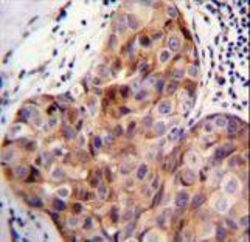

Supportive validation

- Submitted by

- LSBio (provider)

- Main image

- Experimental details

- SCUBE2 Antibody (Center N266) immunohistochemistry of formalin-fixed and paraffin-embedded human breast carcinoma followed by peroxidase-conjugated secondary antibody and DAB staining.